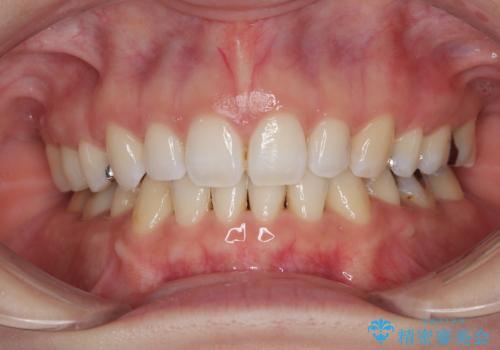

八重歯の再矯正 インビザラインでストレスなく矯正治療

- 学生の頃に矯正治療を行ったものの、保定を怠けてしまったことによる後戻りを気にして来院された患者様です。

根管治療が必要な歯があったため、矯正治療前に根管治療を行い、その後はインビザラインにより矯正治療を行うこととしました。

矯正治療後には根管治療を行った歯の補綴治療を行うこととしました。

下顎の八重歯が上顎歯列に収まる過程で咬みにくさがありましたが、最終的には、咬み合わせも安定し、きれいに歯列を整えることができました。